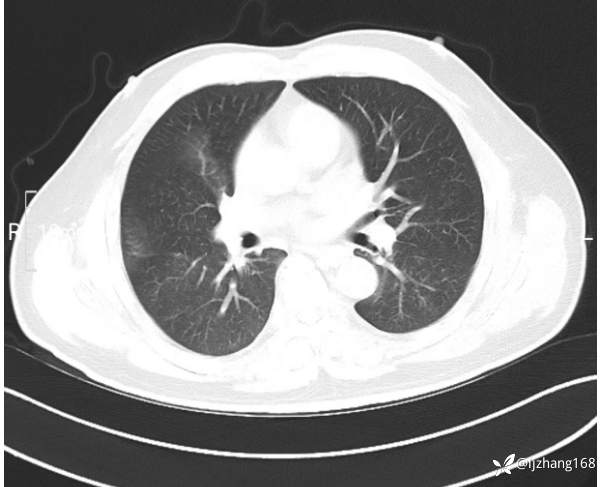

中年男患,右肺团片影,炎症0R肿瘤?

辅助检查:糖化血红蛋白12.3%。肺炎支原体IgG、IgM、呼吸道合胞病毒均未见明显异常。胸部CT:右肺上叶阻塞性肺炎。